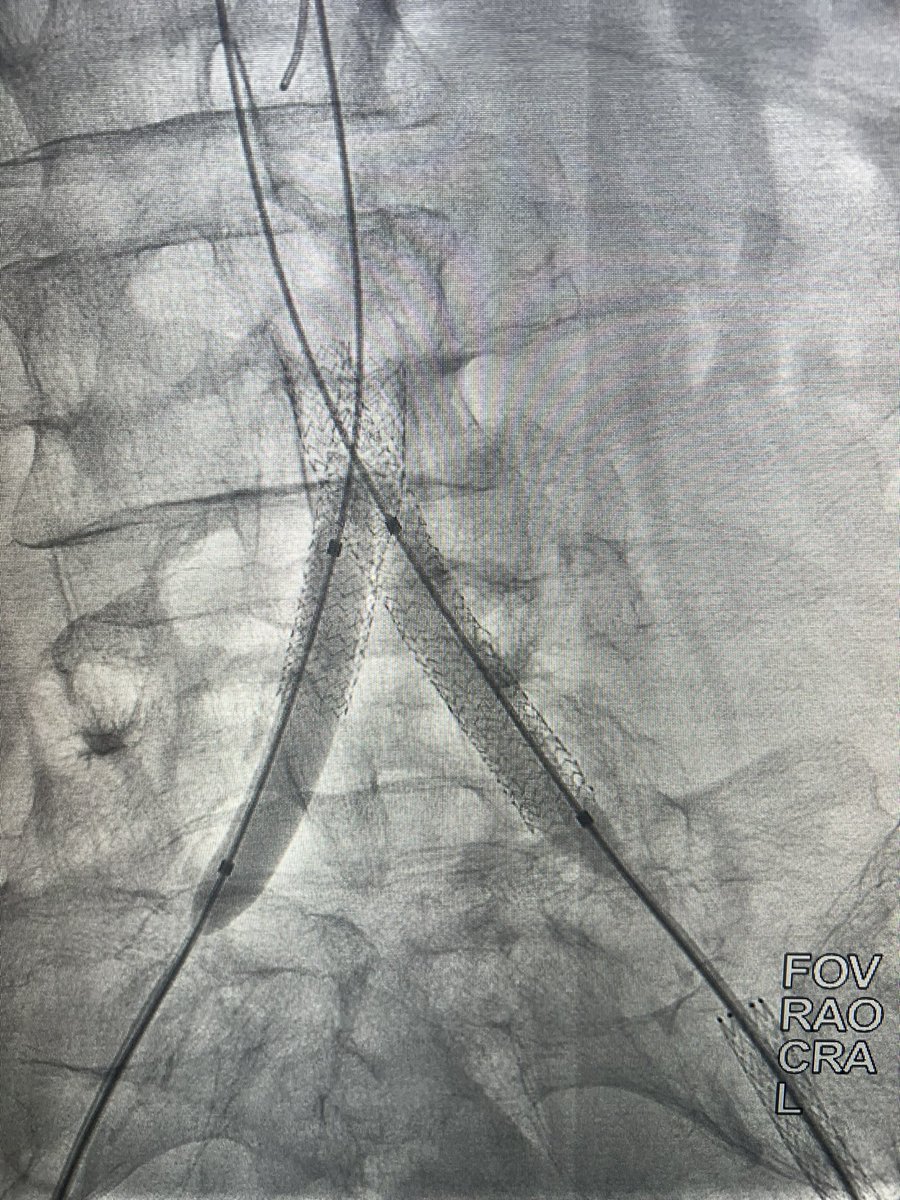

What to do when you can’t get through a distal anastomotic stricture of a thrombosed fem-pop bypass despite lysis? Just open up his native SFA! Special thanks to my fellow, Yusuf @yhkarrar ! UICOMP Radiology SIR RFS Society of Interventional Radiology @

What to do when you can’t get through a distal anastomotic stricture of a thrombosed fem-pop bypass despite lysis? Just open up his native SFA! Special thanks to my fellow, Yusuf @yhkarrar ! <a href="/UICOMPRadiology/">UICOMP Radiology</a> <a href="/SIRRFS/">SIR RFS</a> <a href="/SIRspecialists/">Society of Interventional Radiology</a> @